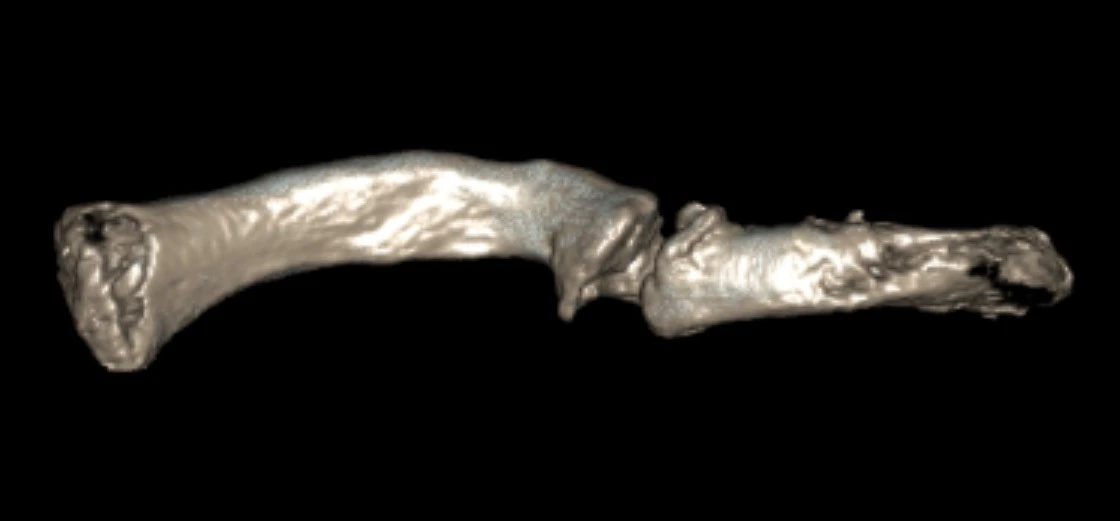

Subsequent imaging confirmed an established hypertrophic non-union of the right clavicle. CT scans and preoperative planning were arranged to assess the feasibility of surgical correction with bone grafting to restore clavicular length. A careful plan was put forward to possibly take down his nonunion, bone graft the defect and replate the clavicle.

This was all done with 3D CT imaging.

Pre op 3D model 1 clavicle nonunion

Pre op 3D model 1

Pre op 3D model 2 clavicle nonunion

Pre op 3D model 2